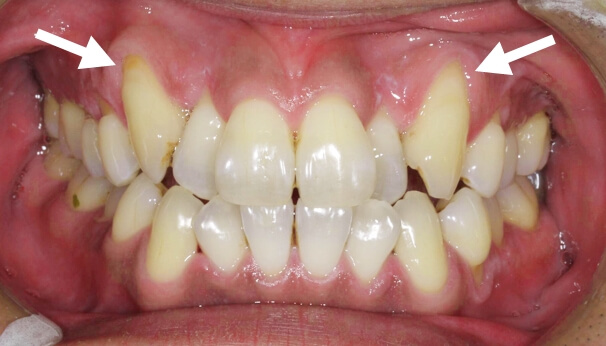

歯周再生治療

審美と健康の⻑期的な両⽴には、健全な⻭周組織と健康的な⻭並びが基本であると考え、

可能な限り天然⻭を保存し、審美と健康の⻑期的な両⽴を⽬指したエビデンス(科学的根拠)に

基づいた治療を基礎研究レベルから実際の臨床まで真剣に取り組んでおります。